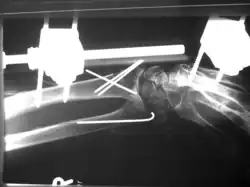

Versorgung durch geschlossene Reposition mit Fixierung durch Kirschnerdrähte

Versorgung durch geschlossene Reposition mit Fixierung durch Kirschnerdrähte -